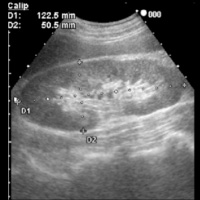

- 腎臓の正常解剖とエコー所見:

- 外側の腎実質の黒い部分:皮質と髄質からなる。CECとの境界が明瞭である。

- 内側の白い部分:腎杯・腎盂と脂肪組織からなる。中心の白色部は、中心エコー帯(CEC:Central Echo Complex)と呼ばれる。

- 慢性腎不全の腎臓のエコー所見:

- 外側の腎実質が白く萎縮し、CECが判別困難になる。

- 一般的に末期腎不全に進むにつれ、腎臓は萎縮し、辺縁の不整や腎実質の菲薄化と輝度上昇を認める。

- やがて透析が始まると、経時的に多数の嚢胞が発生したACDK(多嚢胞化萎縮腎)と呼ばれる形態を呈する。

また、ACDKは腎癌の発生母地となることがある。 - 糖尿病由来の腎不全患者では透析導入直後では腎実質が高輝度になっているだけで健常腎とほとんど変わらないこともある